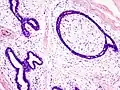

Histopathologic image of breast fibroadenoma. Core needle biopsy. H&E stain.

Fibroadenoma of the breast is a benign tumor composed of a biplastic proliferation of both stromal and epithelial components.[12][13] This biplasia can be arranged in two growth patterns: pericanalicular (stromal proliferation around epithelial structures) and intracanalicular (stromal proliferation compressing the epithelial structures into slit-like spaces).

These tumors characteristically display hypovascular stroma compared to malignant neoplasms.[2][14][9] Furthermore, the epithelial proliferation appears in a single terminal ductal unit and describes duct-like spaces surrounded by a fibroblastic stroma. The basement membrane is intact.[15]